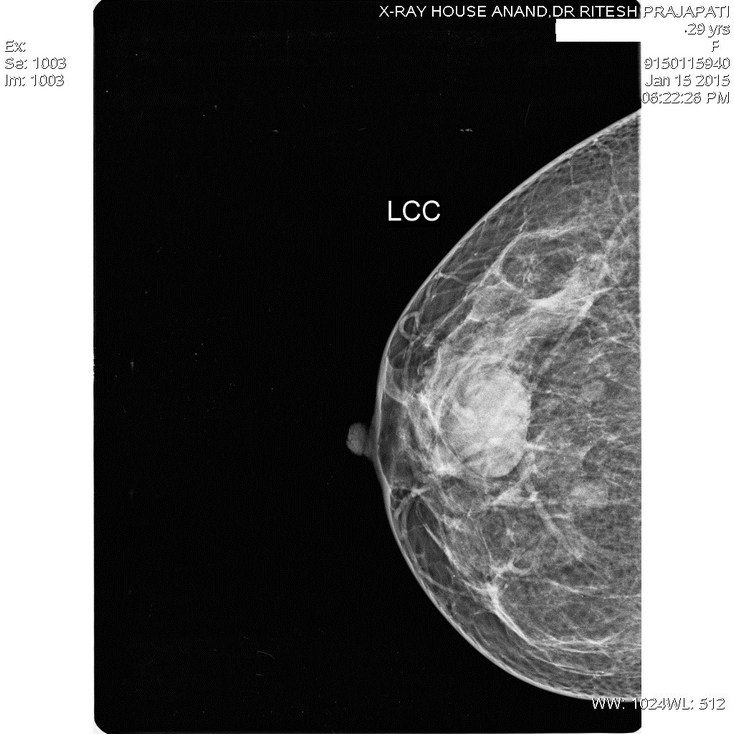

Mammography -Breast Tumor

Mammography-Breast Tumor